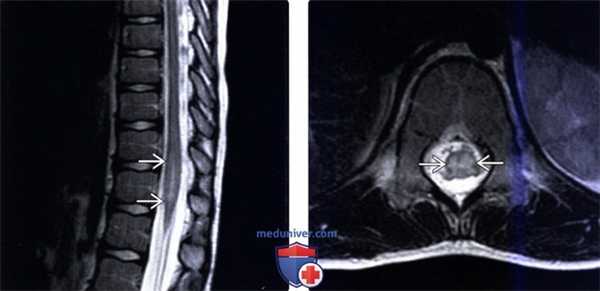

(Слева) Сагиттальный срез Т2-ВИ определяется протяженная гиперинтенсивность Т2-сигнала грудного отдела спинного мозга, захватывающая шесть сегментов. Такая МР-картина центрального отека спинного мозга с относительным сохранением периферических его отделов типична для ОПМ. Артефакт пульсации СМЖ является достаточно частой находкой и напоминает интрадуральное экстрамедуллярное образование.

(Справа) Сагиттальный срез, Т1 -ВИ FS с КУ (этот же пациент): в толще грудного отдела спинного мозга определяется единственный очаг контрастного усиления сигнала, протяженность которого намного меньше протяженности изменений Т2-сигнала.